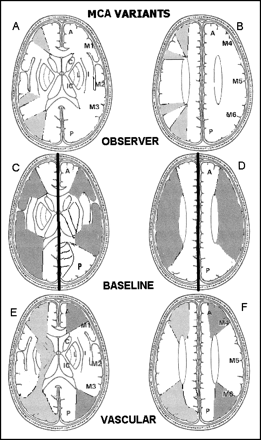

ASPECTS study form and MCA variants.

A and B, Right hemisphere, observer variations: lower and upper ASPECTS slices show as shaded areas the minimal and maximal variations in size of the cortical areas of the MCA (M1–M6) chosen by six expert observers. Left hemisphere, ASPECTS study form: A = anterior circulation; P = posterior circulation; C = caudate head; L = lentiform nucleus; IC = internal capsule; I = insular ribbon; MCA = middle cerebral artery; M1 = anterior MCA cortex; M2 = MCA cortex lateral to insular ribbon; M3 = posterior MCA cortex; M4, M5, and M6 are anterior, lateral, and posterior MCA territories, respectively, approximately 2 cm superior to M1, M2, and M3, respectively, rostral to basal ganglia.

C and D, Cortical MCA area variations with change of baseline. In the right hemisphere, the baseline is parallel to the inferior OML; in the left hemisphere, the baseline is the superior OML.

E and F, Normal vascular variations in MCA size on the two ASPECTS slices. The right hemisphere shows the larger normal variations described by van der Zwan (18) (light shading). The left hemisphere of each shows the smaller, textbook (17), variations (dark shading).

There was at least a centimeter difference in the size of each M area between the minimum and maximum chosen by the observers (Fig 1A and B, right hemisphere). For comparison, the right hemisphere of Figure 1C and D shows the usual MCA territory when the inferior OML is used (15) while the left hemisphere shows it using the superior OML baseline (16). Figure 1E and F shows cross-sectional representations of normal variations in MCA size derived from textbooks (17) in the left hemisphere and from van der Zwan (18) in the right hemisphere.